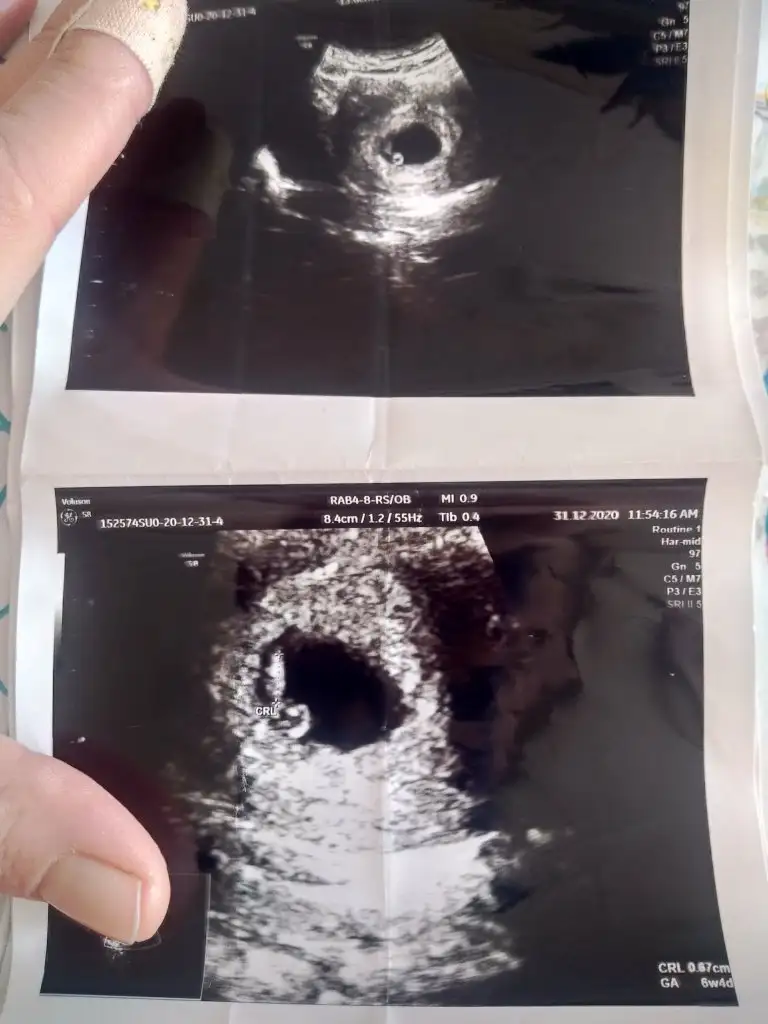

Benimde tahmin edebilir misiniz ilk resim 6 +4 günlük ikinci resim 13 +3

Merhaba bnmde burda 6+2 şuan 9+3 haftalığım çok merak ediyorum bir kızım var bunun cinsiyeti ne olucak diye lütfen bana da söylermisiniz tahmininizi ben hiç anlayamıyorum

• 1614601348870369675027018849708.webp

26,8 KB · Görüntüleme: 107